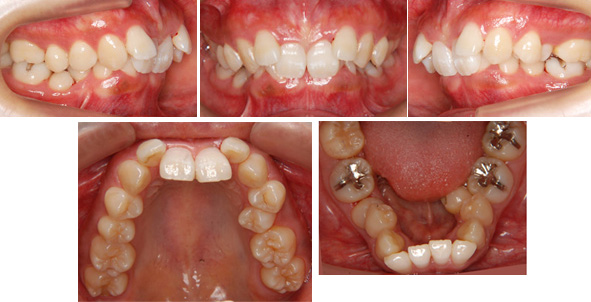

来院時の写真

気になっている点(主訴): 過蓋咬合 飛び出した前歯

正面から上の前歯が下の歯におおいかぶさっていて見えません。

かなり噛みあわせが深いです。もちろん最初からすべての歯に装置は装着できません。

上下の歯列ですが

上顎は2番目の歯(側切歯:そくせっし)が飛び出ています。

下顎の歯列は鞍状型歯列(あんじょうがたしれつ)という歯並びです。

かなりデコボコです。患者さんは成人の女性の方です。

真横から見ると2番目の歯が飛び出ています。こんな感じです。

噛みあわせが深く出っ歯だということがわかります。